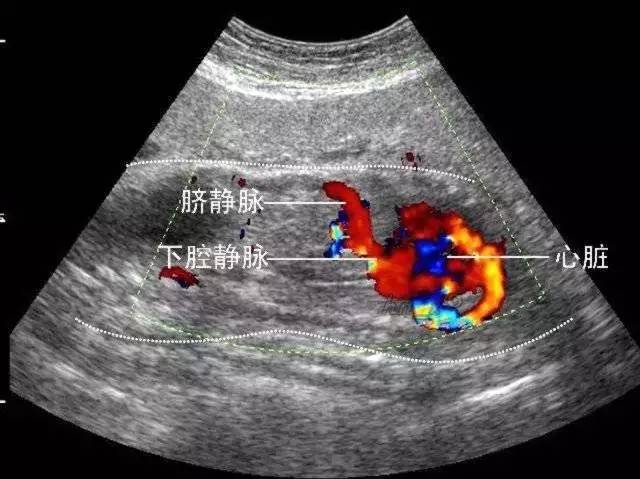

彩超的分辨率一般會(huì)比黑白B超高,而且用彩色標(biāo)注血流,當(dāng)臍帶繞頸的時(shí)候就會(huì)看見(jiàn)胎兒脖子上呈U形或者W形的血流,對(duì)是否臍帶繞頸也就一目了然。